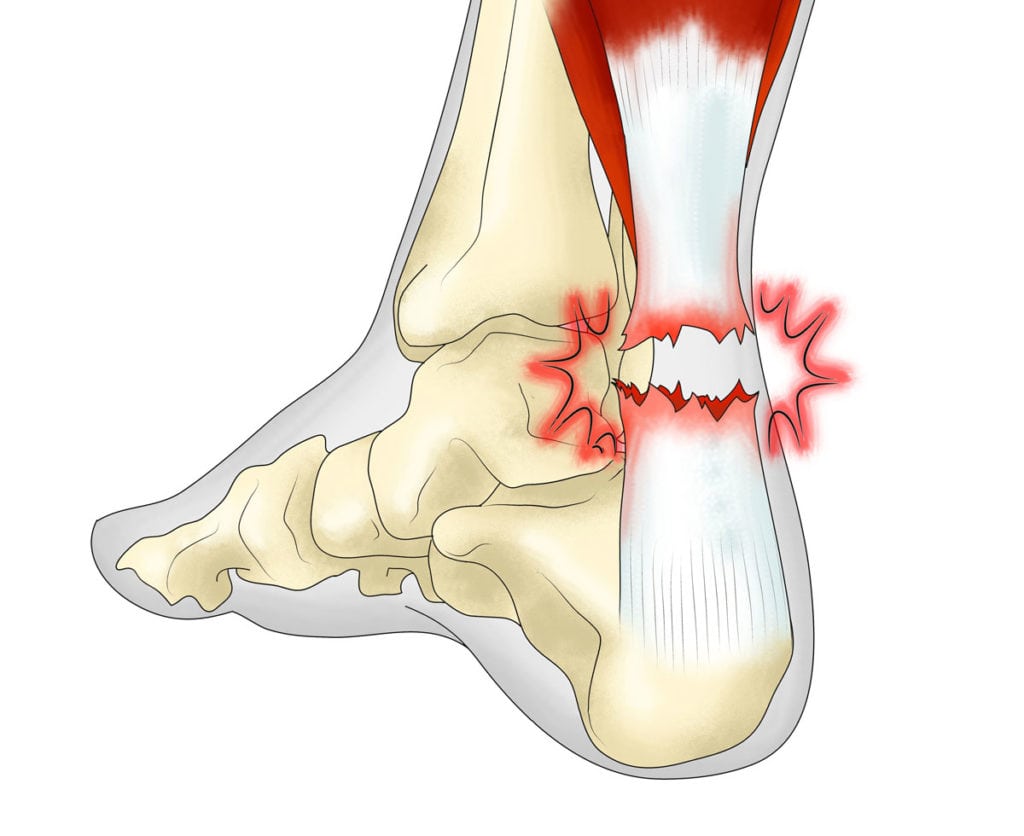

Выраженность симптомов зависит от степени травмы. Но боль в задней поверхности голеностопа в момент травмы возникает всегда. Она бывает настолько сильной, что пострадавший может потерять сознание. Если произошел разрыв большей части соединительнотканного тяжа, то боль не ослабевает, а усиливается из-за сдавливания воспалительным отеком чувствительных нервных окончаний. Повреждение сопровождается хрустом, напоминающим звук переламывающихся сухих веток. Для растяжения ахиллова сухожилия характерны следующие симптомы:

- небольшое кровоизлияние или обширная гематома, формирующаяся в течение нескольких часов;

- отек, образующийся сначала сзади голеностопного сустава, а затем распространяющийся на лодыжку и стопу;

- «провал» в области расположения ахиллова сухожилия, часто свидетельствующий о его полном отрыве от костного основания;

- невозможность сгибания стопы из-за острой боли и в результате утраты этой функции соединительнотканным тяжом.